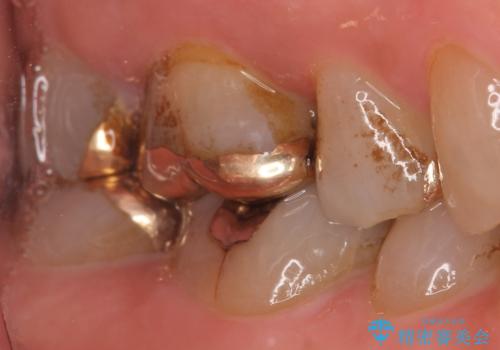

- 冷たいものがしみる右上の奥歯を治療して欲しいといらっしゃった方の症例です。

右上6,7の金歯を外したところ、虫歯が歯茎より深い位置まで進行していたため歯周外科を行いました。

虫歯が進み歯茎より深くなってしまうと、虫歯を取り残してしまうリスク、樹脂の硬化の妨げ、補綴物の不適合、歯肉炎・歯周病のリスクの増大等様々な弊害が起こり得ます。

そのため当院では歯周外科手術(歯茎を下げる手術)や歯の挺出による、虫歯が歯茎より深いという問題の解決を推奨しております。